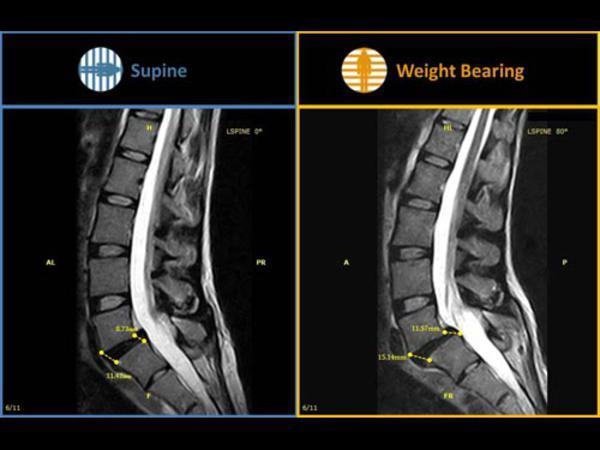

Фото отчет о прошедшем мероприятии: